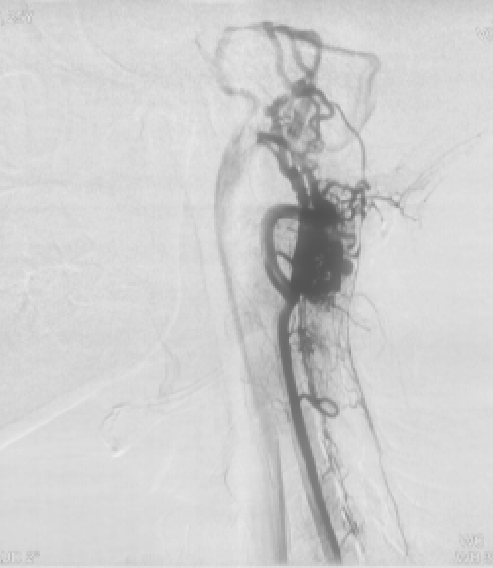

图2:术前DSA正侧位显示延髓至颈3水平畸形血管团

图3:术后复查显示切除畸形血管团后 (对比图2)

神经外科王贵怀主任经过认真仔细的评估后,决定进行血肿清除和畸形血管切除术,再造脊髓髓内的血流。术后由神经外科神经介入专家苏伟医师给予复查血管造影,显示畸形血管基本全切,症状明显好转,住院2周已能下地自主活动,姑娘愁苦的脸上终于露出了笑容。